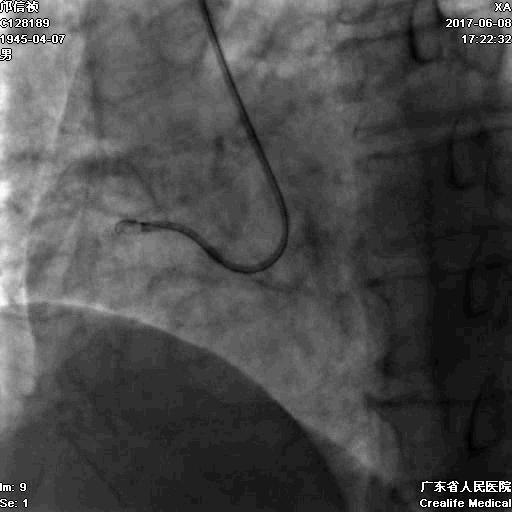

第二步:处理LCX

Fielder XT-A,Gaia First ---在微导管支撑下通过闭塞病变

LCX植入支架

2.0*10mm球囊

2.75*22mm药物支架